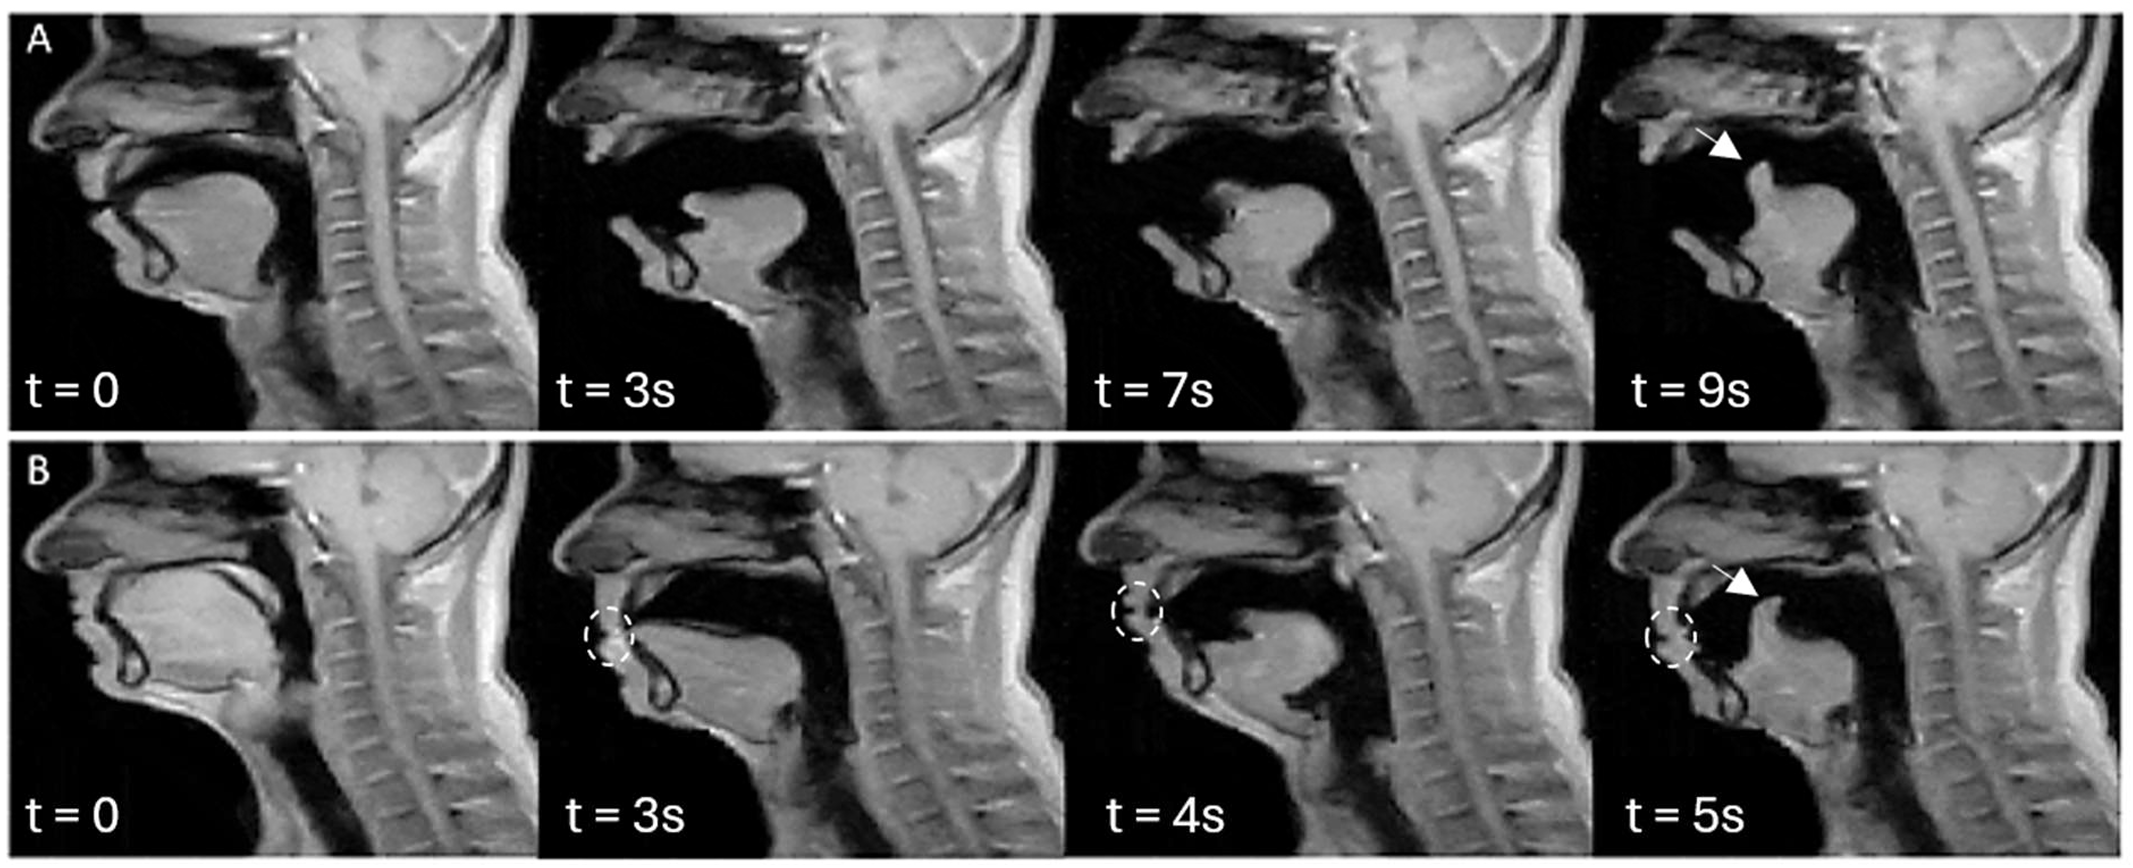

Although there are still questions regarding why people yawn, scientists have discovered that yawning occurs in nearly all mammals, and most mammal species are capable of spreading the behaviour to one another. The UNSW team systematically studied the physiology of yawning, normal breathing, a deep breath, and suppression of yawns through scanning volunteers.

“The yawn seems to be creating a flow of CSF away from the brain, whereas taking a deep breath causes a flow of CSF towards the brain,” Martinac claimed. “This was an unexpected finding for us.” Cerebrospinal fluid (CSF) surrounds and cushions the brain and spinal cord, as well as providing nutrients to the nervous system and assisting with the removal of waste. When someone takes a deep breath, their cerebrospinal fluid moves towards the brain. However, the fluid moves away from the brain while yawning.

The change in blood flow and pressure during yawning and taking a deep breath is also evident in the images. During yawning, there was an increase in blood flowing from the brain through the veins in the neck, creating space for fresh blood to enter the brain through the arteries.

Blood flow does not reverse direction when yawning, but during the initial phase of a yawn, the blood flow into the brain through the carotid arteries increases by 30%. Such an increase in blood flow into the brain during yawning indicates that yawning has a greater effect on circulation than just one factor.

Finally, the research team noted that each participant had his or her own unique yawning style. Each person’s motion of his or her jaw and tongue was consistent each time he or she yawned. Even when the participant attempted to hold back the yawn, the same pattern of motion was observed. This suggests that yawning is controlled by inherent wiring in the brain rather than learned behaviour.